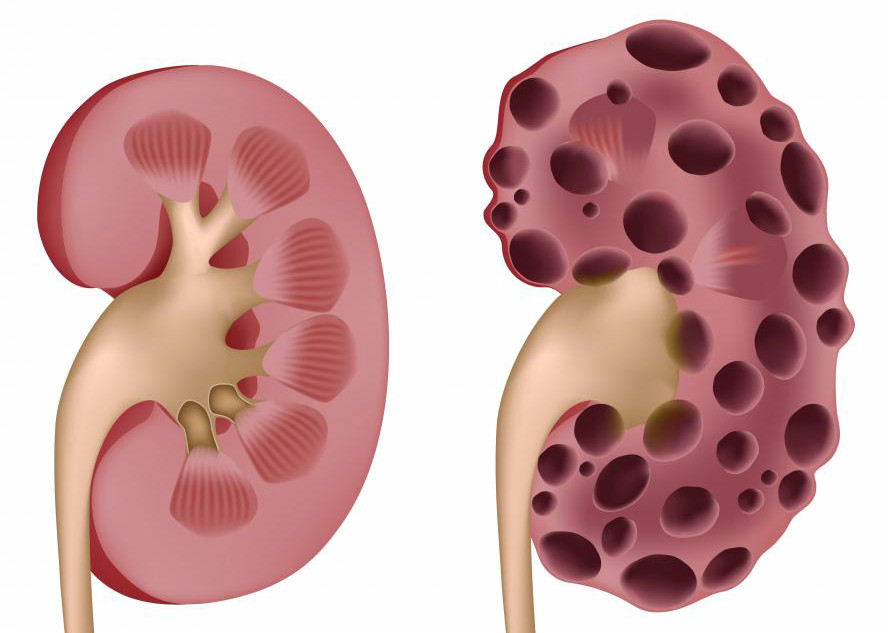

Хроническое тубуло-интерстициальное воспаление проявляется изменениями в составе мочи и симптомами артериальной гипертензии. Появление белка в моче часто связано с легкой гематурией. Камни в моче обычно не обнаруживаются, однако наблюдается чередование полиурии и олигурии. Часто выявляется двустороннее кистозное поражение. Артериальная гипертензия поддается медикаментозному лечению. Если стандартные гипертензивные препараты неэффективны, это может указывать на развитие гломерулосклероза — сужения почечной артерии.

- поликистоз почек;

Уратный нефролитиаз и хронический нефрит часто возникают на фоне длительного течения тофусной подагры с частыми обострениями. В некоторых случаях нефропатия может стать первым сигналом подагры, особенно если наблюдается нетипичная форма артрита, проявляющаяся воспалением крупных суставов и выраженными болевыми ощущениями.